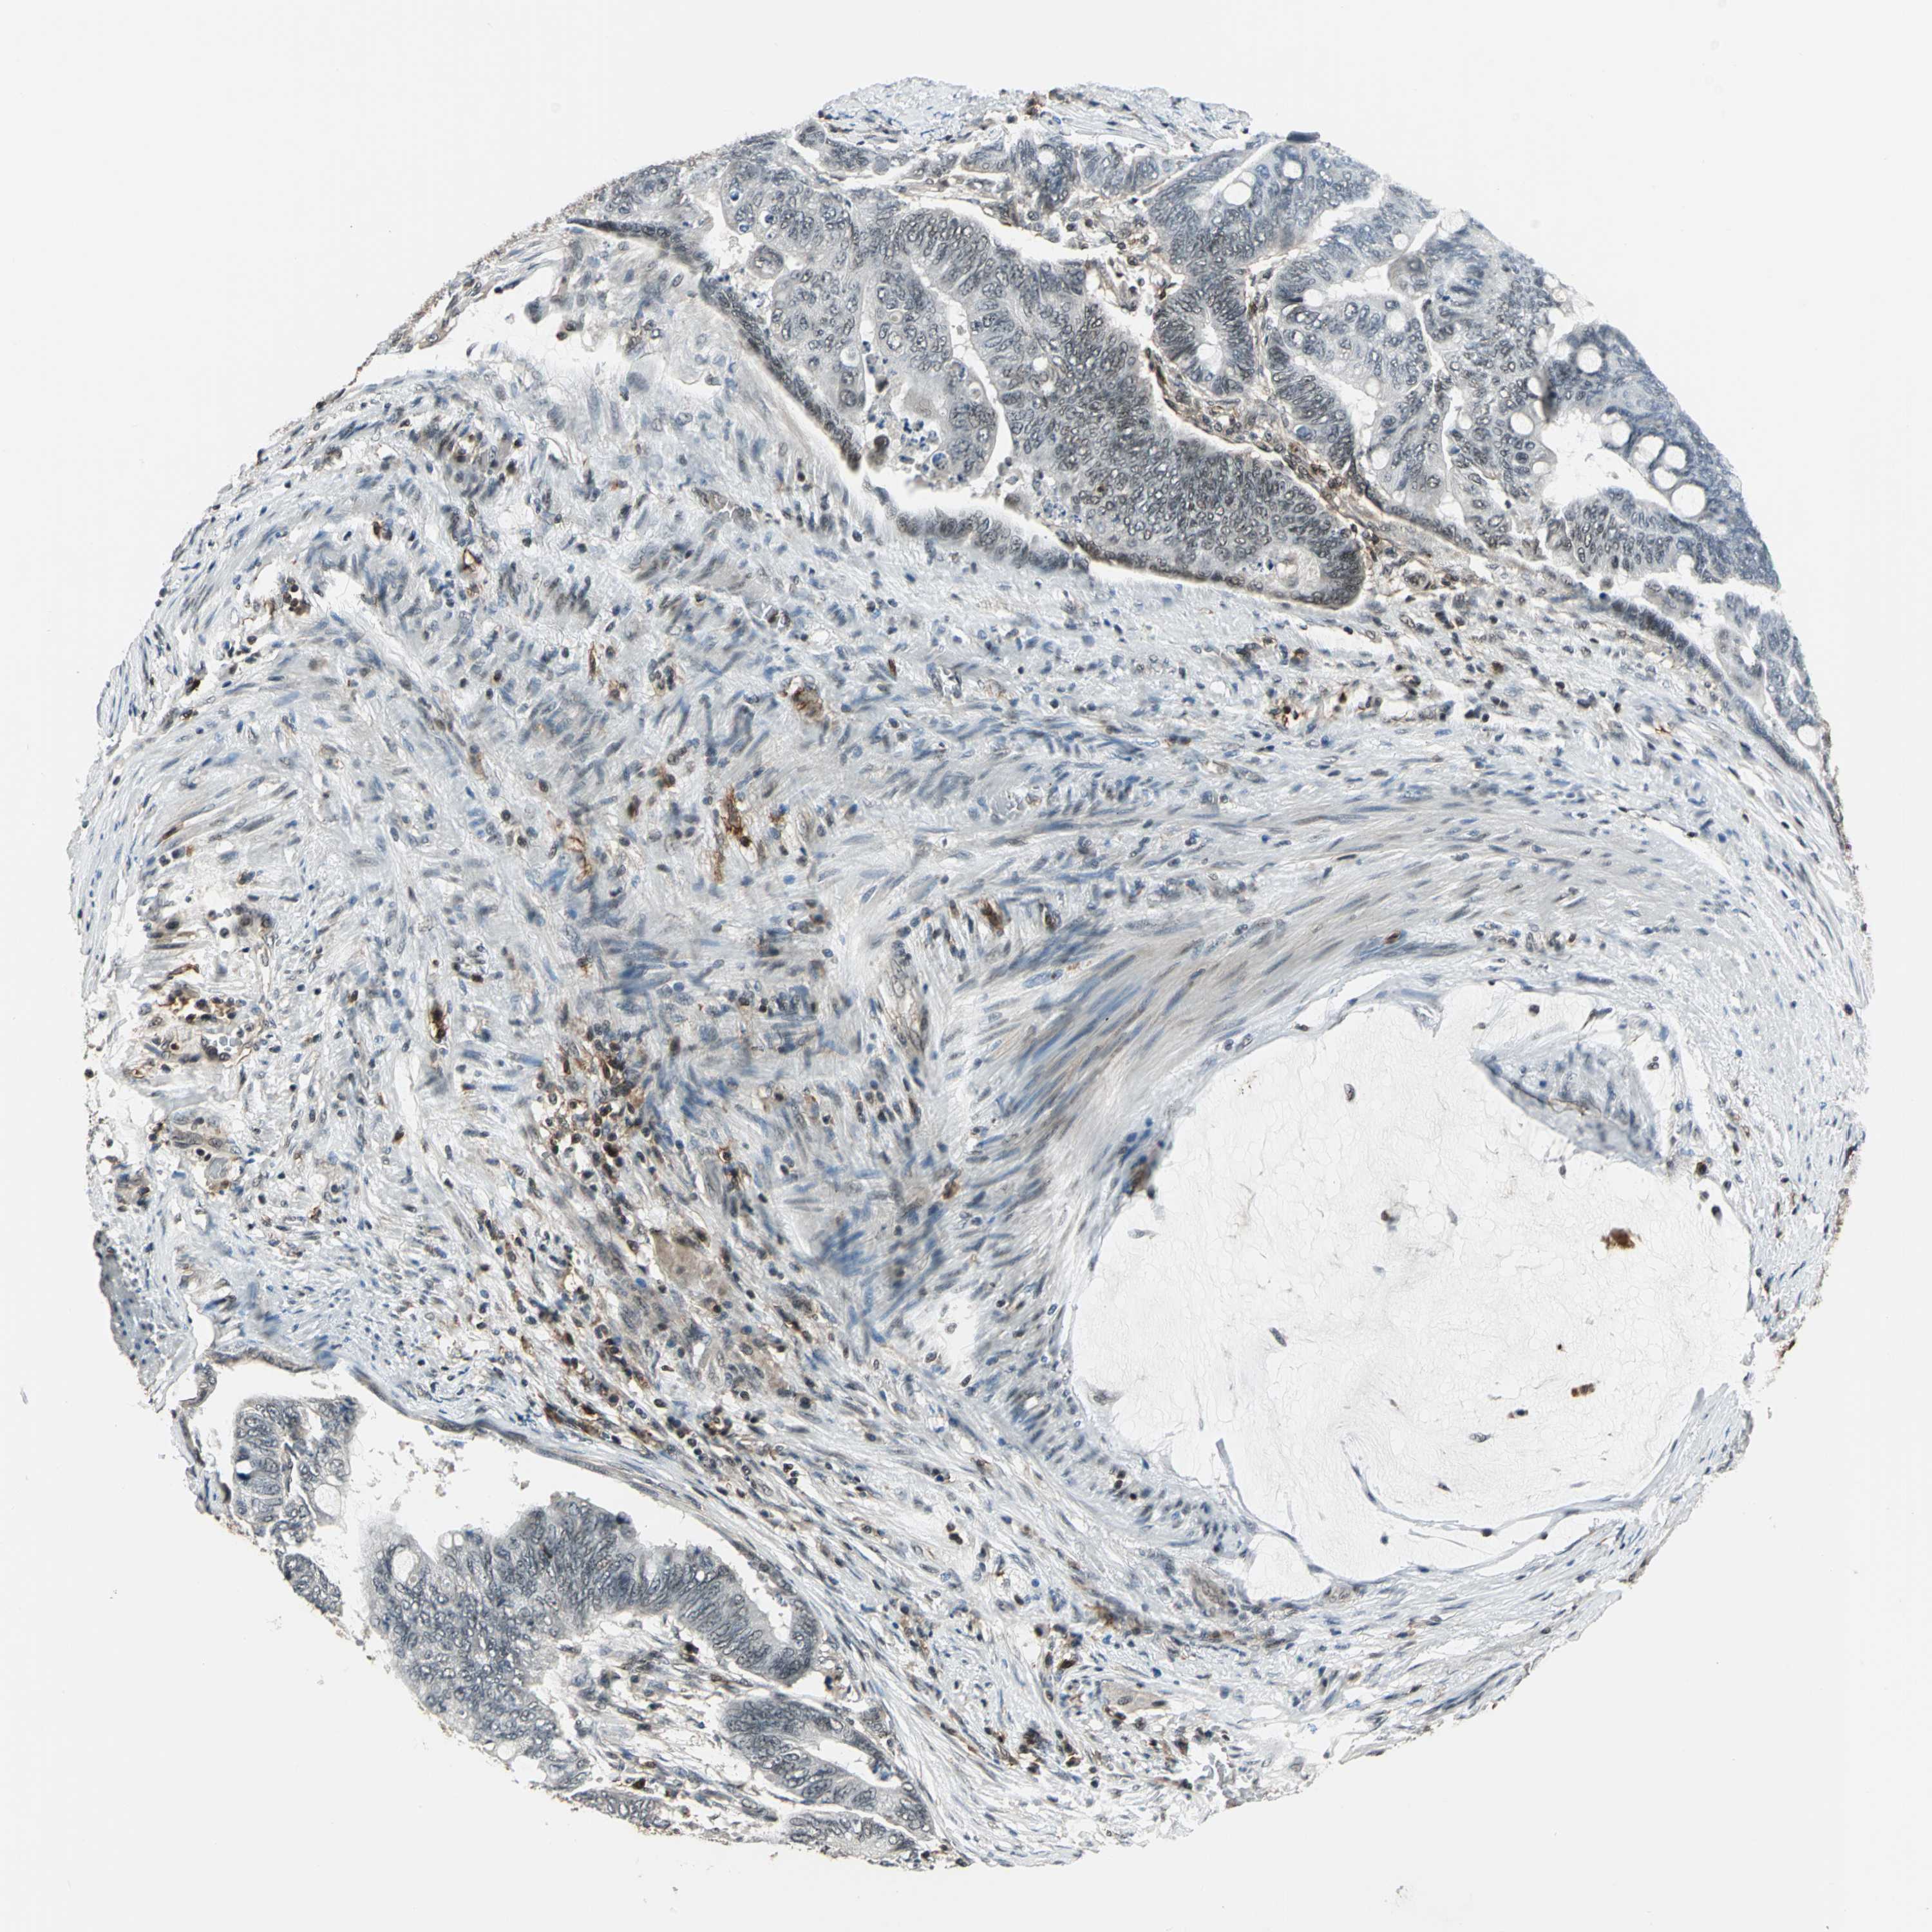

CANCER COLORECTAL CANCER Show tissue menu

Colorectal cancer

Human cancer

Colon adenocarcinoma

Rectum adenocarcinoma